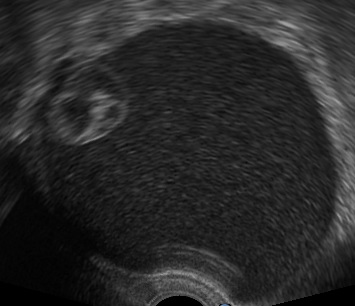

Ultrasound findings

- Frequently large, unilateral, cystic mass.

- Usually multilocular.

- Smooth walls.

- Contains small cystic components or honeycomb-like loculi.

- Intralocular fluid of varying echogenicity.

- Linear calcifications (rare).

- Papillary projections (rare).

- Mucinous ascites may present after cyst rupture.